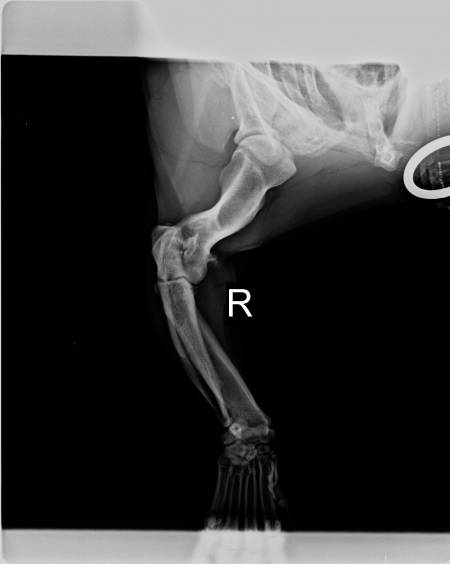

wie einige von euch ja wissen, war ich heut mit Sammy bei Dr. Thiet in Isernhagen in der Kleintierklinik um Sammy seine Krummbeine zu röntgen. Ich hatte ja Angst, dass die Beine sich noch weiter nach aussen drehen könnten, was zum Glück nicht bestätigt wurde. Soviel dazu.Hier erstmal die Röntgenbilder:

Der Arzt hat gesagt dass Elle und Speiche glücklicherweise im richtigen Winkel nebeneinander liegen aber dass er eine Entzündung am Gelenk entdeckt hat.

Um die Herkunft der Entzündung genauer zu bestimmen, müsste mit Sammy ein CT gemacht werden. Er würde sonst aufschneiden müssen um genauer zu schauen, aber er würde gern erst genau wissen (durch das CT) was diese Entzündung auslöst.Komischerweise hat er mir gegen diese Entzündung nichts gegeben (fällt mir jetzt erst auf wo ich zu Hause bin) und mir bloß gesagt, dass ich mir das mit dem CT noch überlegen kann (300,-€ !!!) da es jetzt nicht unbedingt so akut sei und Sammy ja keine Schmerzen hat. Ausserdem soll ich die Stellung seiner Pfoten beobachten und ihn keine Treppe mehr herunterlaufen lassen. Daran halte ich mich jetzt auch.